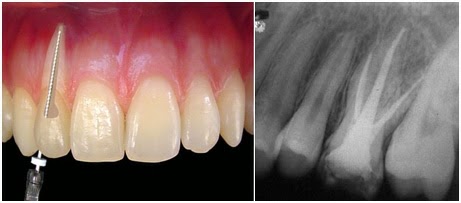

*Tratamento de Canal

Tratamento de Canal